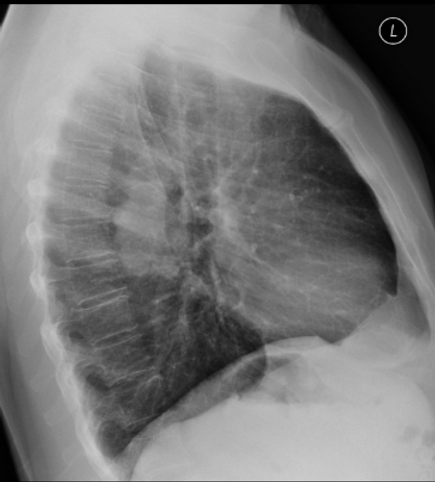

Lateral View

Case courtesy of Emma Gevorgyan – Radiopaedia.org. From the case rID: 1022

Left Lower Lobe Lung Cancer

Lobulated soft tissue mass lesion is noted posterior to the left hilum on imaging

Concurs with chronicity and symptoms in clinical history.